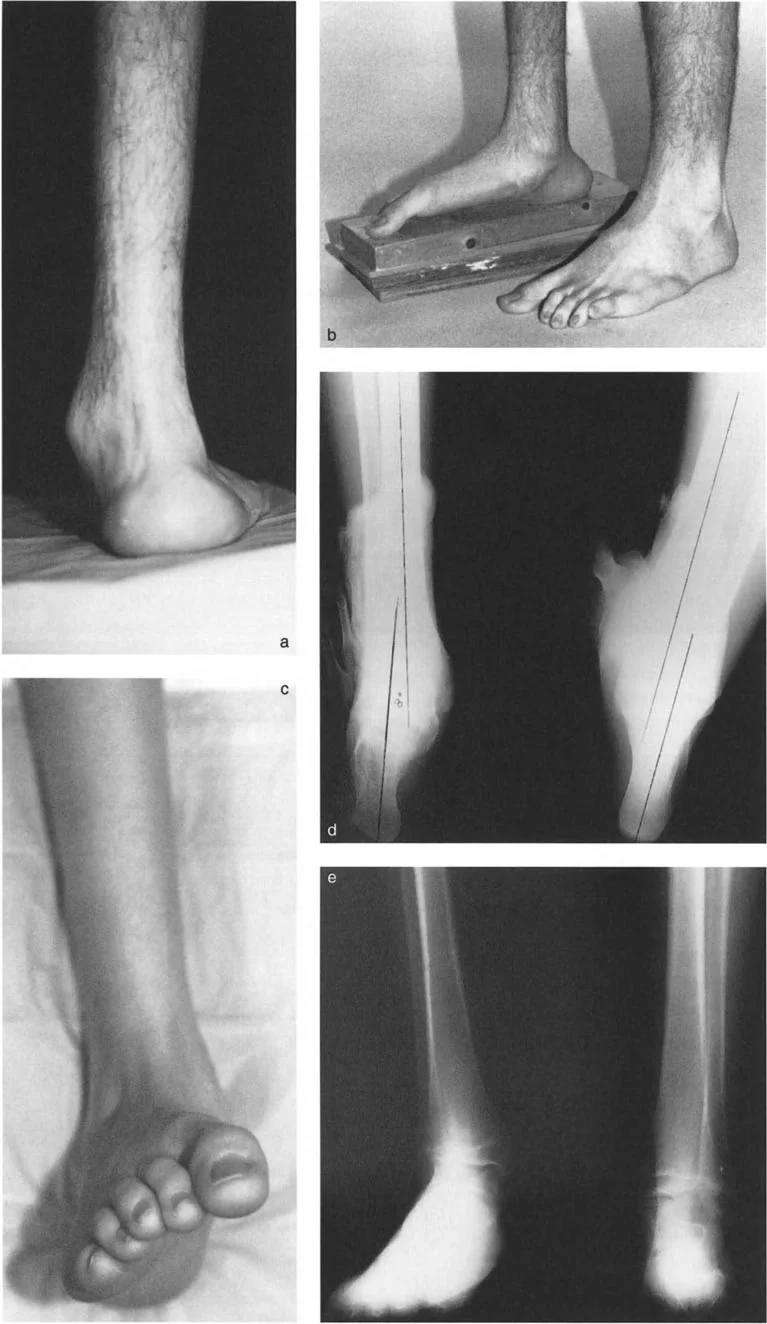

* المعاينة البصرية: ملاحظة شكل الساق والقدم والكاحل أثناء الوقوف والمشي. يتم تقييم العرج، وتوازن الجسم، وكيفية توزيع الوزن.

* فحص المشي (Gait Analysis): ملاحظة نمط مشي المريض لتحديد كيفية تأثير التشوه على حركته.

* تقييم تعويضات القدم: يتم تقييم كيف تحاول القدم تعويض التشوه في الساق. على سبيل المثال، في تشوه التقوس الساقي، قد تظهر القدم بقوس عالٍ وصلب. في تشوه الروحبة، قد تظهر القدم مسطحة ومرنة.

* الأشعة السينية (X-rays) الواقفة لكامل الطرف السفلي: هذه الأشعة ضرورية لتقييم المحاذاة الكلية للطرف السفلي تحت تأثير وزن الجسم. يطلب الأستاذ الدكتور محمد هطيف صورًا شعاعية كاملة الطول للساق أثناء الوقوف (Full-length standing alignment films) لتقييم المحور الميكانيكي للساق وتحديد زوايا المفاصل بدقة.